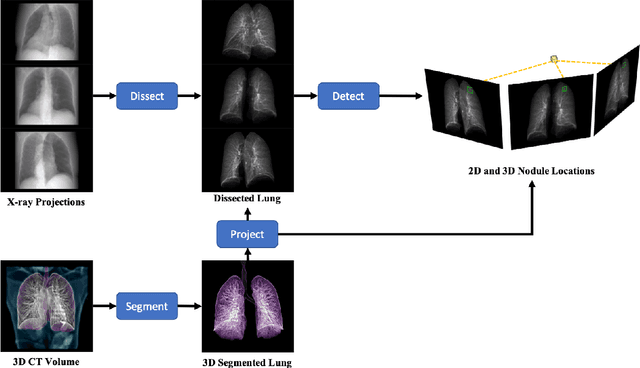

Abstract:Although radiographs are the most frequently used worldwide due to their cost-effectiveness and widespread accessibility, the structural superposition along the x-ray paths often renders suspicious or concerning lung nodules difficult to detect. In this study, we apply "X-ray dissectography" to dissect lungs digitally from a few radiographic projections, suppress the interference of irrelevant structures, and improve lung nodule detectability. For this purpose, a collaborative detection network is designed to localize lung nodules in 2D dissected projections and 3D physical space. Our experimental results show that our approach can significantly improve the average precision by 20+% in comparison with the common baseline that detects lung nodules from original projections using a popular detection network. Potentially, this approach could help re-design the current X-ray imaging protocols and workflows and improve the diagnostic performance of chest radiographs in lung diseases.